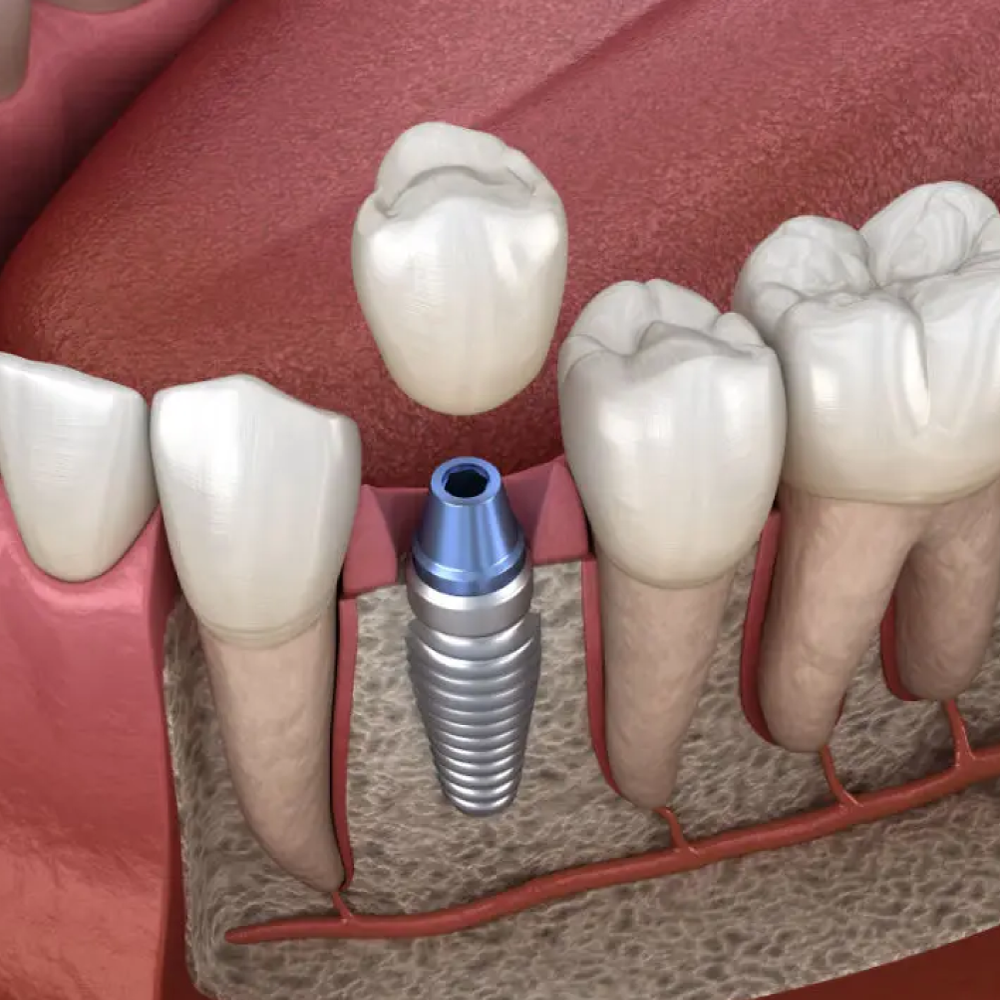

- Funcionalidad Restaurada